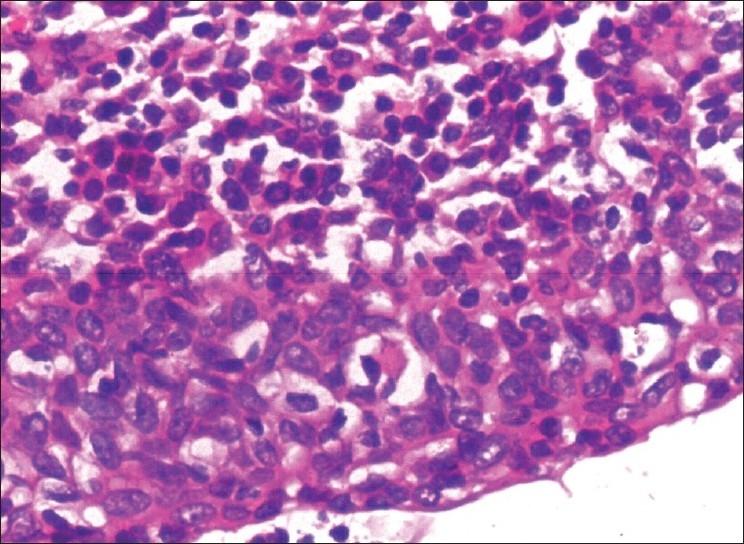

Lymphoepithelial cyst - A sign of unappreciated HIV infection.

Indian J Sex Transm Dis AIDS. 2011 Jan;32(1):60-2. doi: 10.4103/0253-7184.81263.

https://cdn.ncbi.nlm.nih.gov/pmc/blobs/6926/3139296/d90daa3af214/IJSTD-32-60-g002.jpg

https://cdn.ncbi.nlm.nih.gov/pmc/blobs/6926/3139296/db72f3f375ff/IJSTD-32-60-g001.jpg